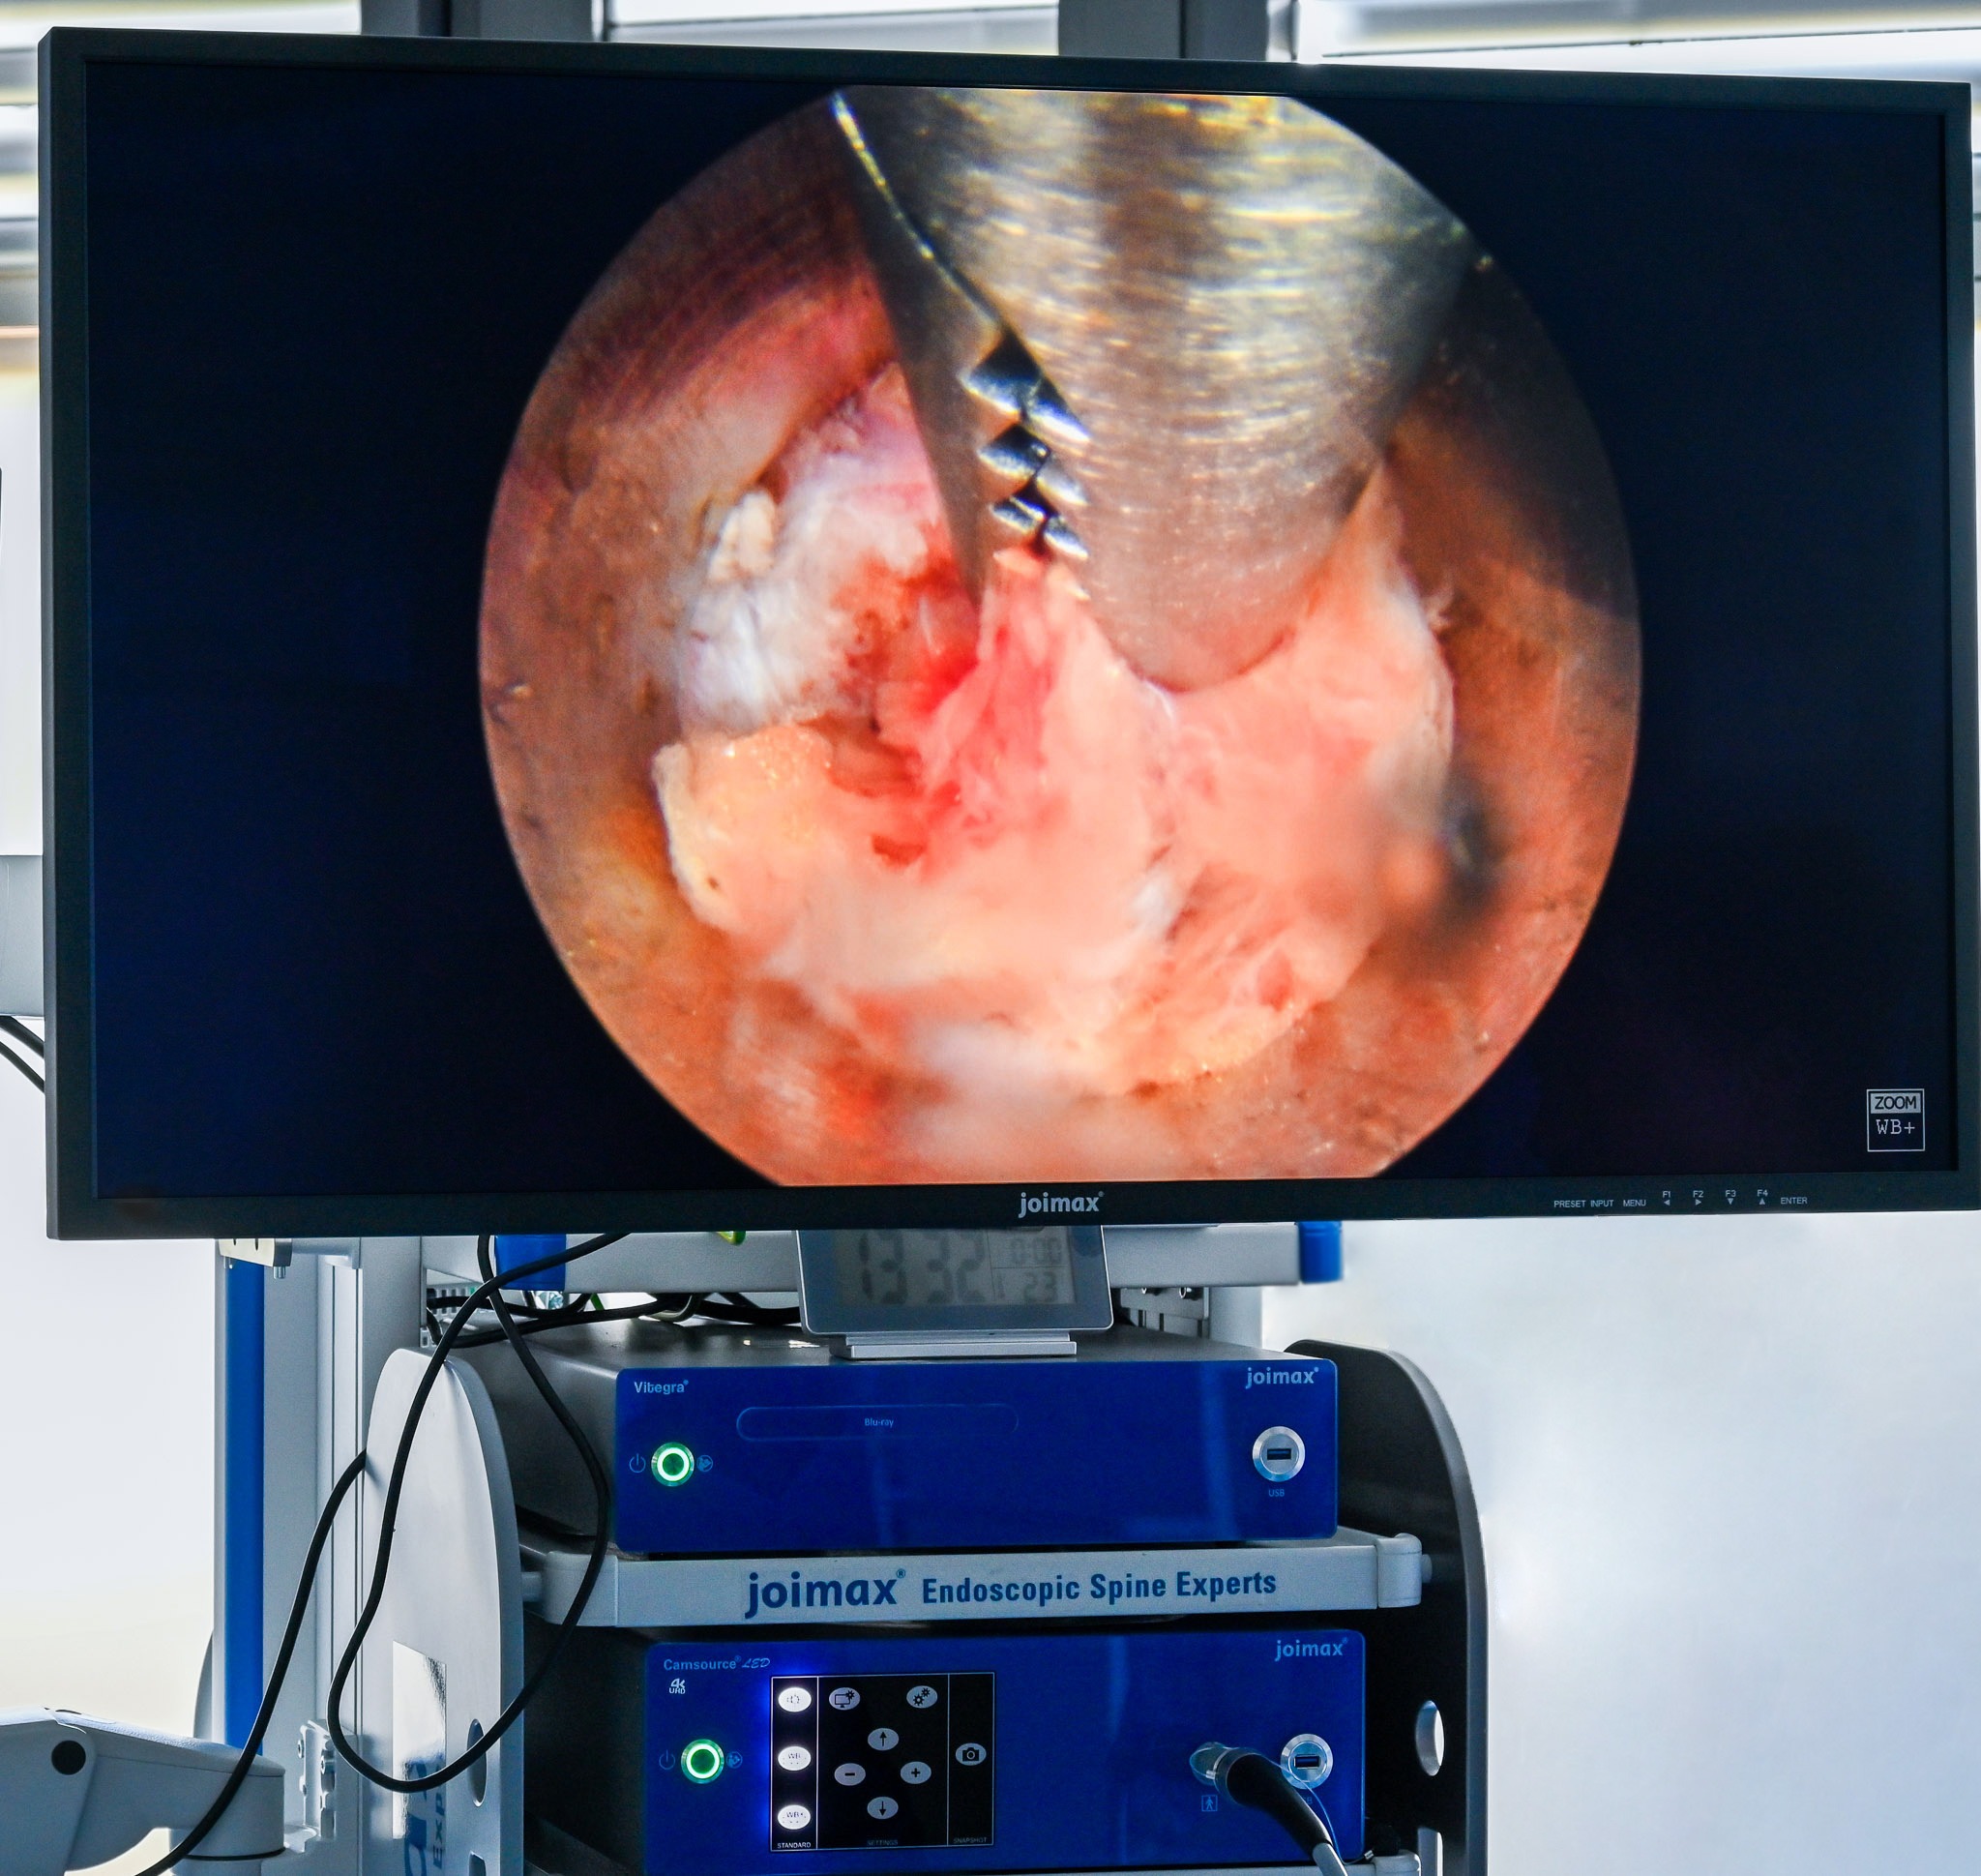

Camsource®- Camera & Light Source System

The imaging system is the heart of endoscopic spine surgery. A combination of high-resolution image processing and brilliant optical performance are necessary to safely navigate the anatomy of the spine and capture even the smallest structures. To achieve this, joimax® imaging components – from endoscope over camera to monitor – are developed not as individual products, but as a cohesive, integrated system – each with the goal of highest performance and clearest vision. Our latest 4K imaging solutions reveal even smallest details and create an almost spatial visual impression.

joimax® offers complete and integrated solutions for minimally-invasive endoscopic spinal care. The Camsource® Duo expands our existing imaging portfolio offering brilliant imaging.

Excellent Image and Outstanding Illumination

The Camsource® Duo features finer details due to 3-chip sensors capturing more light. Excellent differentiation between varying colors enables clear identification of the anatomical structures.

Whether ultrasound, X-ray or endoscopy: The best examination technique is only as good as the display used for visualization. For the new Camsource® Duo, joimax® offers a 32“ and a 43“ 4K display which presents the joimax® Camsource® Duo as a Ultra High Definition System.

The Camsource® LED 4K offers high resolution imaging with the latest CMOS technology to provide brilliant images, especially in combination with joimax® 4K endoscopes and the 4K flat screen monitors. The constantly high color temperature of the new LED light source ensures an ideal and realistic color reproduction of every endoscopic intervention.

Perfect images to support endoscopic spine surgery – because illumination, optical system and image processing are ideally matched.

Together with the 4K Camsource® LED, Camsource® Duo and the 4K UHD Display, joimax® offers a complete optical solution with superior image quality for endoscopic spinal surgery.